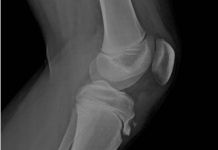

Osteoartrite: gradi, sintomi, trattamento

L'osteoartrite è una malattia cronica delle articolazioni associata a cambiamenti degenerativi e distrofici delle loro strutture, che interessano principalmente la cartilagine. La malattia ha...